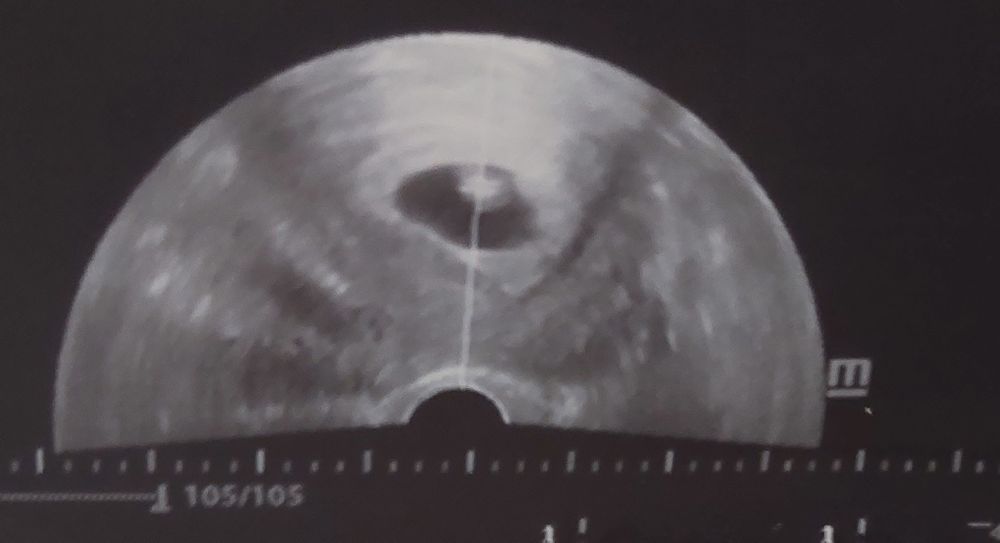

Все хорошо, сердце бьётся, посмотрели на мониторе пульсацию, послушали ритм 😊, а сейчас статистика:

▪︎ ПЯ 23 [соответствие 6н4д]

▪︎ ЖМ 3.9

▪︎ КТР 7.2

▪︎ ЧСС 133

Располагается по задней стенке.